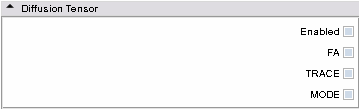

- Diffusion Tensor panel: